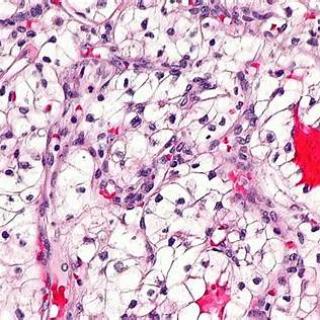

Высокодифференцированная аденокарцинома представляет собой злокачественную опухоль железистого происхождения, клетки которой сохраняют значительную часть признаков нормальной ткани, поэтому опухоль часто растёт медленнее и даёт меньше ранних метастазов по сравнению с низкодифференцированными вариантами